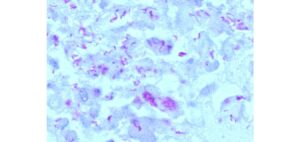

Distinguishing between Mycobacterium infections causing feline tuberculosis lesions by Jordan Mitchell and colleagues at the University of Edinburgh.

Mycobacterium bovis and M. microti cause tuberculosis (TB) in a wide range of animals. Both produce identical macroscopic lesions, but they differ with respect to their zoonotic potential. This BSAVA PetSavers-funded study compared histological and immunohistochemistry patterns of feline TB granulomas to help differentiate between the two causes of TB in cats.